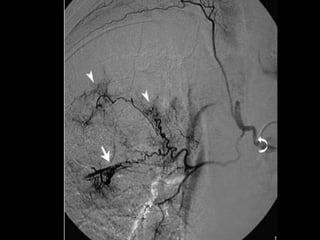

Bronchial artery embolization